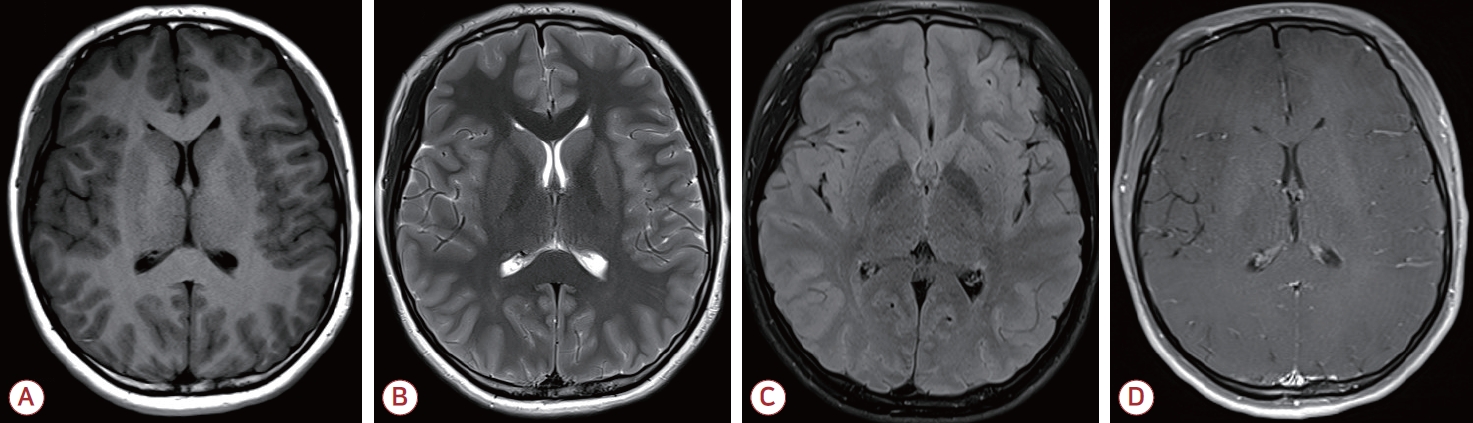

19세 여자가 갑자기 발생한 의식 변화를 주소로 응급실에 왔다. 의식은 멍하고 정신기능의 속도가 저하되어 반응이 느렸으며 상황에 적절한 대답을 하지 못하는 혼돈 상태를 보였다. 신경계진찰에서 퍼덕떨림(flapping tremor)을 보였고 다른 이상 소견은 없었다. 가족력에서 의식 변화를 유발할 만한 특이 병력은 확인되지 않았다. 과거력상 4-5세경 수일 동안 멍하고 반응이 떨어지는 증상을 보였으나 특별한 조치 없이 회복된 적 있었고, 당시 특별한 진단은 받지 못하였다고 하였다. 이후 현재까지 정상적인 발달 과정을 거쳤으며, 특이 병력이나 현재 복용 중인 약물은 없는 상태이다. 뇌 조영증강 전산화단층촬영 및 뇌 조영증강 자기공명영상에서 구조적 이상 소견은 없었으며(Fig. 1), 뇌척수액 검사에서 뇌압은 150 mmH2O, 백혈구 1/mm3, 총 단백질 28.3 mg/dL, 포도당 71 mg/dL, 혈청포도당 118 mg/dL로 중추신경계 감염 및 염증의 증거는 없었다. 혈액 검사에서는 간기능은 정상이나 혈중 암모니아 농도가 290 μg/dL로 정상 수치의 4-5배가량 상승하여 있었다. 이에 대해 복부 조영증강 전산화단층촬영을 시행하였으나 간 및 간문맥 등의 구조적 이상은 보이지 않았다(Fig. 2). 뇌파 검사에서는 전반적인 세타파(theta slowing, 4-7 Hz) (Fig. 3-A)를 보여 고암모니아혈증으로 인한 대사 뇌병증(metabolic encephalopathy) 진단하에 경구 락툴로스(lactulose) 투약을 시작하였다. 그 외 국소 시작발작이 발생하였을 가능성을 배제할 수 없어 레비티라세참(levetiracetam) 투약도 같이 시작하였다. 입원 2일째 추적 혈액 검사에서 혈중 암모니아 수치는 174 μg/dL로 감소하였으며, 의식 수준도 명료하게 평소와 같은 수준으로 회복되었다. 추적 뇌파 검사도 정상이었다(Fig. 3-B).

Figure 2.

Abdomen-pelvis computed tomography (A) Pre-contrast phase, (B) arterial phase, (C) portal venous phase. There is no structural lesion such as liver cirrhosis, portosystemic shunt.